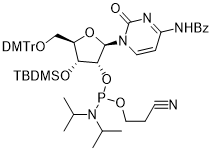

馬鞍山致研生物醫(yī)藥科技有限公司成立于馬鞍山市鄭浦港新區(qū)現(xiàn)代產(chǎn)業(yè)園。公司專(zhuān)注于生物小分子、醫(yī)藥中間體相關(guān)產(chǎn)品的研發(fā)和生產(chǎn),產(chǎn)品主要包括DNA亞磷酰胺單體、RNA亞磷酰胺單體、特殊單體以及按照客戶(hù)要求定制的RNA和DNA,并且公司提供定制合成等方面的研究服...

馬鞍山致研生物醫(yī)藥科技有限公司成立于馬鞍山市鄭浦港新區(qū)現(xiàn)代產(chǎn)業(yè)園。公司專(zhuān)注于生物小分子、醫(yī)藥中間體相關(guān)產(chǎn)品的研發(fā)和生產(chǎn),產(chǎn)品主要包括DNA亞磷酰胺單體、RNA亞磷酰胺單體、特殊單體以及按照客戶(hù)要求定制的RNA和DNA,并且公司提供定制合成等方面的研究服...